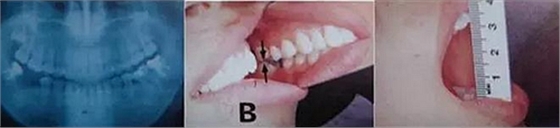

圖1. 磨牙部咬合崩潰導(dǎo)致的顳下頜關(guān)節(jié)部位和肌肉系統(tǒng)的病理性狀況的誘發(fā)。

圖9. 上頜和下頜第二磨牙中發(fā)生的前方誘導(dǎo)干擾引發(fā)的張口困難。

下頜磨牙的遠中頰側(cè)牙尖的近中頰側(cè)斜面和上頜磨牙的近中頰側(cè)牙尖的遠中腭側(cè)斜面相接觸。

圖10. 不考慮下頜第三磨牙的咬合平面破壞的修復(fù)體制作完成后,

后方磨牙干擾引發(fā)的前方誘導(dǎo)干擾。